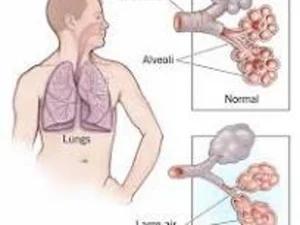

Which symptoms does Luanne demonstrate that indicate early signs of emphysema? Select all that apply.

1. Barrel chest

2. Increased morning mucus production

3. Increasing shortness of breath when climbing stairs

4. Production of dark yellow green sputum

5. Wheezing with exhalation

Luanne's provider perscribes a chest X-ray and PFT. The confirm that she is at a moderate Stage 2 disease with forced expiratory volume in one second FEV1 65% of normal. Luanne has many questions, how should the nurse respond?

3. The chest Xray shoes damage to the air sacs in your lungs.

7 -